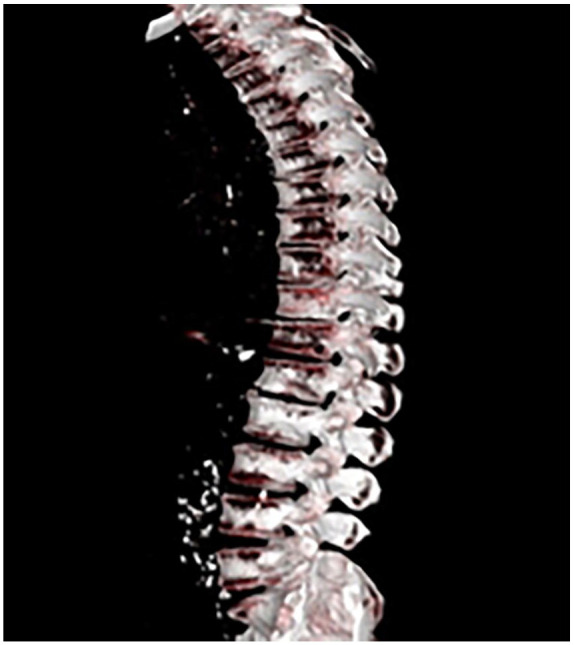

Diabetes mellitus is associated with an increased risk of osteoporosis and fractures due to impaired bone metabolism and increased fall risk. This case report highlights a 49-year-old Palestinian man with long-standing poorly controlled type 2 diabetes who presented with progressive back pain following a hypoglycemic syncopal episode. Clinical assessment and imaging, including magnetic resonance imaging (MRI) and Dual-Energy X-ray Absorptiometry (DEXA), confirmed a vertebral compression fracture at D12-L1 and severe osteoporosis. Laboratory investigations ruled out secondary causes of osteoporosis. The patient was treated with zoledronic acid, pain management, and improved glycemic control, leading to symptom relief and better metabolic outcomes after 6 months. This case underscores the importance of early osteoporosis screening in diabetic patients and highlights the need for an integrated approach to managing both diabetes and bone health to prevent fractures in high-risk individuals.